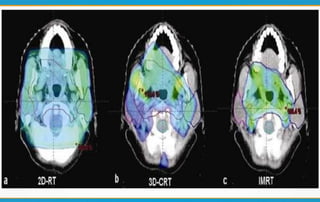

Conventional Radiotherapy

1) Uses a number of coplanar beams.

2) Beam shaping by using customized blocks.

3) Use of wedges for producing desired dose distribution.

3D – Conformal Radiotherapy

1) Uses 3D planning techniques & special delivery systems to shape the

fields – to reduce normal tissue damage close to the target volume.

2) Uses a larger number of beams.

3) Beam shaping done by MLC s.

Intensity Modulated Radiotherapy

1) Large number of beams are used from different directions.

2) Each beam divided into number of beamlets whose intensity can be

modulated.

3) Intensity modulation & beam shaping done by MLC s.